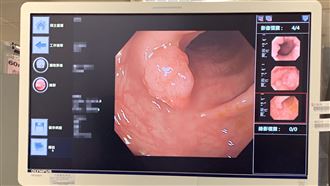

大腸癌6危險因子 濫用抗生素「破壞腸道菌相」成隱形地雷

資深藝人余天和李亞萍的二女兒余苑綺(改名余泳澐)勇敢抗癌8年不敵直腸癌擴散病逝,享年39歲。大腸直腸癌蟬聯14年國內十大癌症發生人數之冠,每年約有1.7萬人確診。肝病防治學術基金會公布大腸癌6大風險因子,「抗生素濫用」竟上榜。(記者:陳弋)